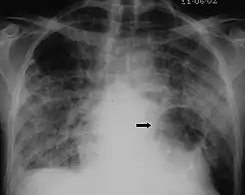

The diagnosis can be confirmed by the characteristic appearance of the chest X-ray and an arterial oxygen level (PaO2) that is strikingly lower than would be expected from symptoms. Gallium 67 scans are also useful in the diagnosis. They are abnormal in about 90% of cases and are often positive before the chest X-ray becomes abnormal. Chest X-ray typically shows widespread pulmonary infiltrates. CT scan may show pulmonary cysts (not to be confused with the cyst-forms of the pathogen).

Chest X-ray of increased opacification (whiteness) in the lower lungs.

X-ray of a cyst in pneumocystis pneumonia[6]